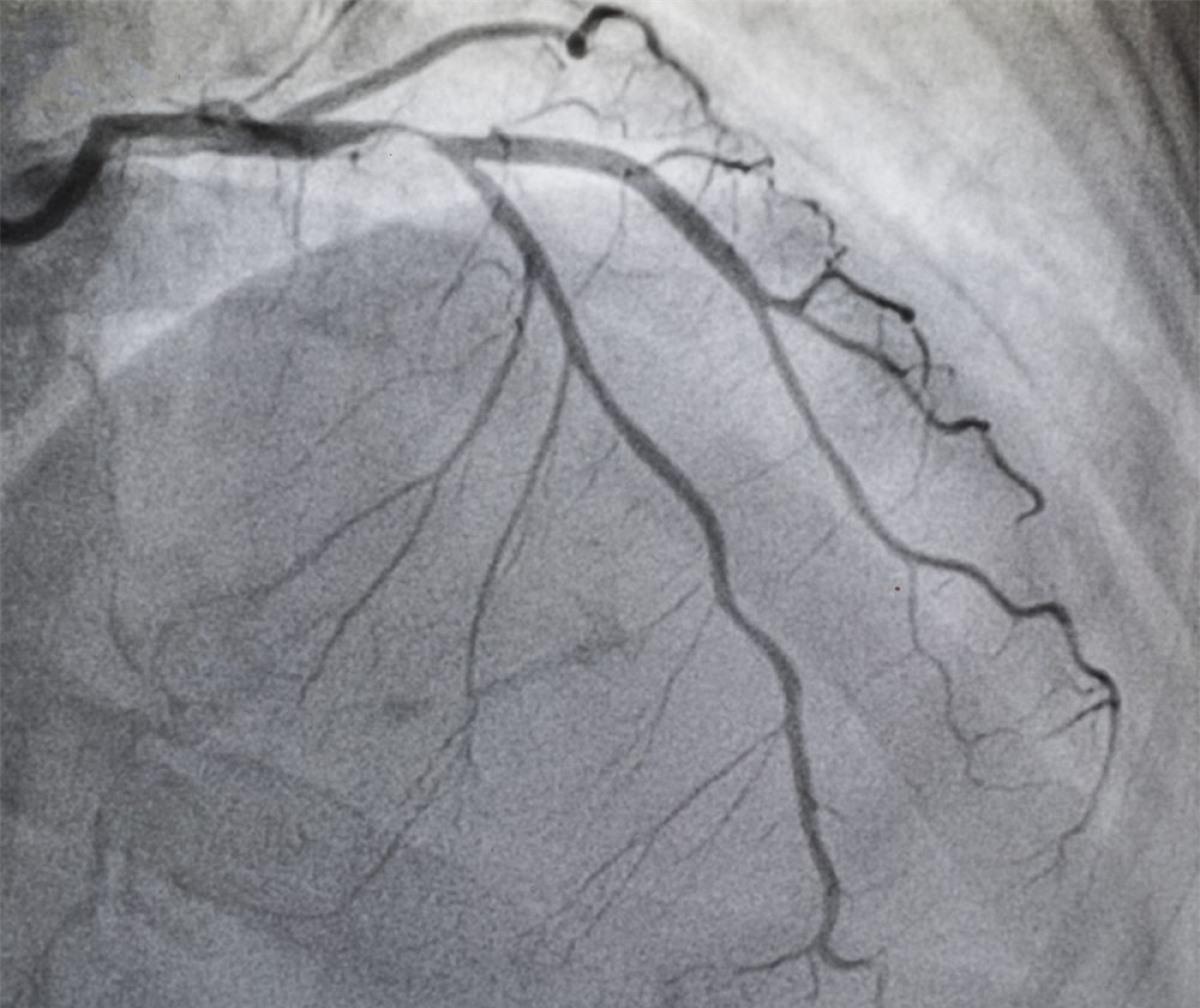

Bệnh mạch vành: Bệnh mạch vành hay bệnh động mạch vành là một trong những nguyên nhân gây tử vong hàng đầu trên thế giới. Bệnh mạch vành và đột quỵ đã gây ra cái chết của 15,2 triệu người vào năm 2016. Để giảm nguy cơ mắc bệnh này, tốt nhất bạn nên ăn uống và tập luyện điều độ, tránh xa thuốc lá và rượu bia.